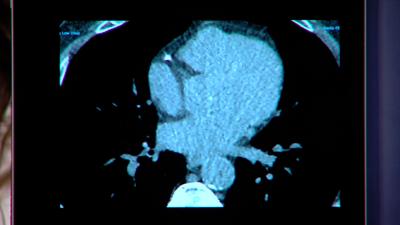

Heart scans

This proposal requires private individual and group insurance providers to cover heart scans for adults 40 and older when recommended by healthcare providers.

SPRINGFIELD, Ill. (WAND) — The Illinois House unanimously passed legislation Tuesday to require insurance companies to cover preventative heart scans.